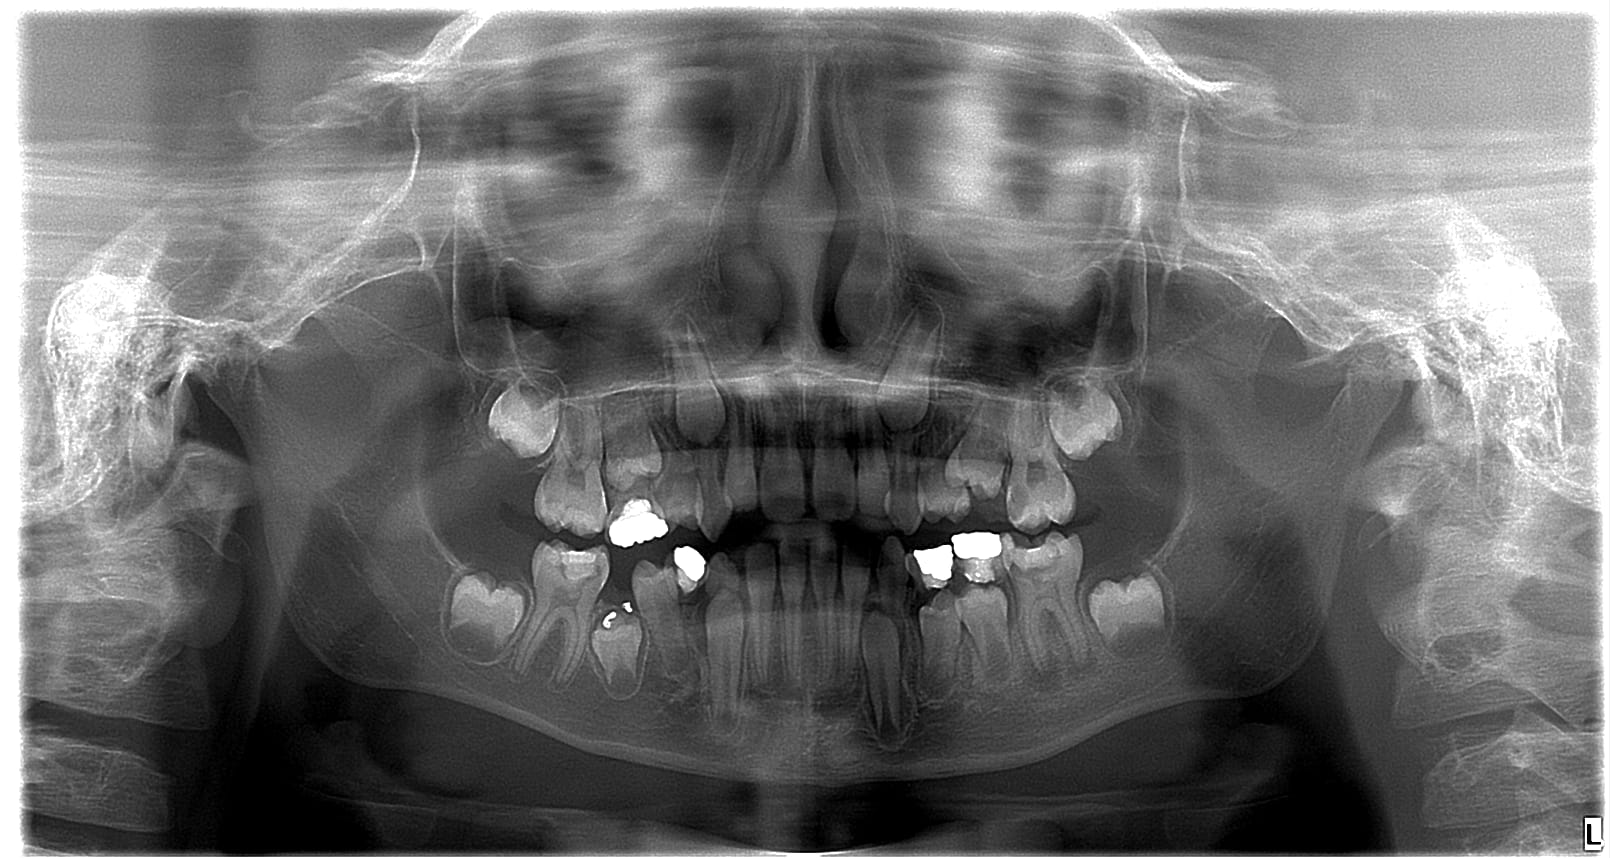

Première patiente:

8 ans.

Soins sous anesthésie générale à 4 ans.

Surprise. 36 qui a eu un composite il y a quelques mois. Hum hum.

26, la petite carie mésiale en bouche est en fait un trou en sous-gingival. Surprenant vu que le test au froid était normal.

Oh, des dents de lait à dégager.

Et c'est quoi ce merdier au dessus de 45 ? Pourquoi que j'y vois rien en bouche ?